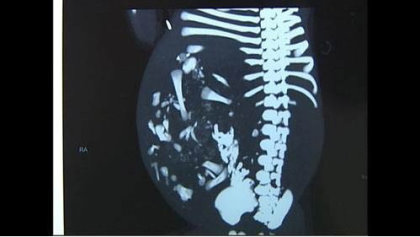

女嬰被送醫檢查,醫生發現女嬰肚裏有個巨大腫瘤,幾乎佔據腹腔三分之二的空間。醫生表示,若不及時取出,嬰兒可能因為腫瘤壓迫、血供不足,出現腸梗塞,甚至有生命危險。不過由於腫瘤十分巨大,新生嬰兒尚不足月,手術風險極大。

最後專家耗時2小時,替這名剛出生8天的女嬰進行腹腔腫瘤切除手術,從肚裏取出一個直徑約16公分的腫瘤。原來這個「腫瘤」是個寄生胎,又叫「胎中胎」,是個並未發育完全的胎兒,但已可看到小手、小腳、指甲、頭髮、脊柱等器官。醫生量了一下,這個寄生胎重達900克,但女嬰本身的體重只有2.7公斤。